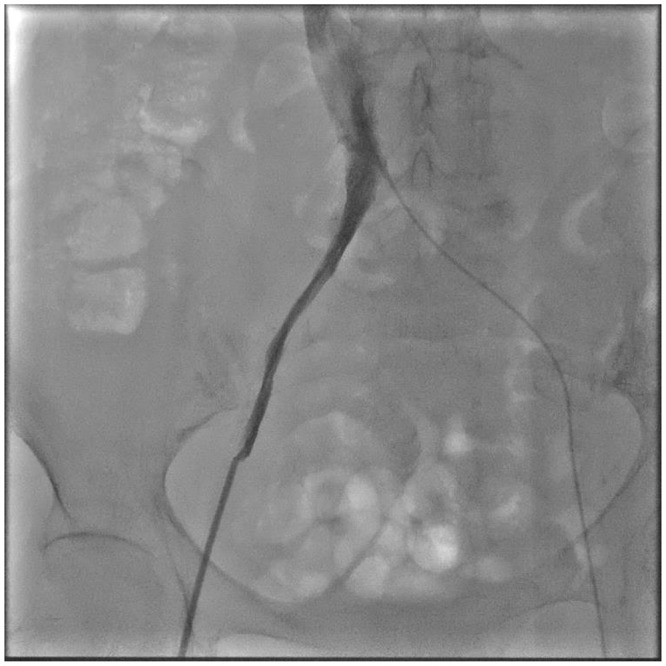

Case presentation: We report the case of a 74-year-old female with sick sinus syndrome, chronic kidney disease, type 2 diabetes, and severe bilateral iliac vein stenosis, who was deemed high-risk for conventional pacemaker implantation. After failed attempts through both femoral veins, the right internal jugular vein (RIJV) was successfully used as an alternative access route for Micra leadless pacemaker implantation. The procedure was performed under ultrasound and fluoroscopic guidance without complications. Post-procedure, the pacing threshold was 0.75 V, sensing was 8.5 mV, and impedance was 760 Ω, all within normal limits.